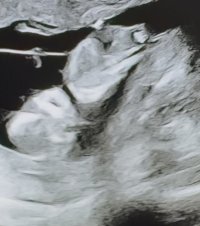

Veldig utydelig NUB, men tipper guttVis vedlegget 474235

Noen som vil gjette?

TIpper guttVis vedlegget 474235